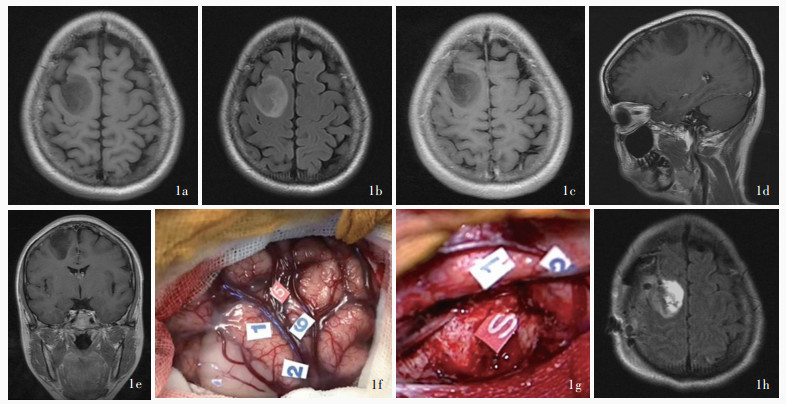

Gao H , Bai HM , Wang LM , Zhang XP , Wang GL , Wang YB , Li TD , Wang WM . Surgical strategy of a Chinese - English - French multilingual patient with tumor in eloquent area. Zhonghua Shen Jing Yi Xue Za Zhi, 2011, 10: 688- 692.

doi: 10.3760/cma.j.issn.1671-8925.2011.07.010

高寒, 白红民, 王丽敏, 张小鹏, 王国良, 王玉宝, 李天栋, 王伟民. 汉-英-法多语者脑功能区手术定位的探讨. 中华神经医学杂志, 2011, 10: 688- 692.

Gao H , Bai HM , Han LX , Li TD , Wang GL , Wang WM . Brain cancer surgery in the language areas of Mandarin - Cantonese bilinguals. J Cancer Res Ther, 2015, 11: 415- 419.

doi: 10.4103/0973-1482.151932

Bai HM , Wang WM , Li TD , Lin J , Gao H , Wang LM , Xia LH , Xie XM . Maximally safe resection of gliomas near eloquent areas through intra - operative direct electrical stimulation. Zhonghua Shen Jing Wai Ke Za Zhi, 2012, 28: 1210- 1214.

doi: 10.3760/cma.j.issn.1001-2346.2012.12.007

白红民, 王伟民, 李天栋, 林健, 高寒, 王丽敏, 夏丽慧, 谢学敏. 应用术中直接电刺激最大安全切除功能区胶质瘤. 中华神经外科杂志, 2012, 28: 1210- 1214.

Bai HM , Wang WM , Li L , Wang GL , Li TD , Gao H , Wang LM , Liu XH , Zhang LH . Application of intraoperative subcortical mapping by direct electrical stimulation for maximal safe resection of diffuse low - grade gliomas near eloquent areas. Zhonghua Shen Jing Wai Ke Za Zhi, 2014, 30: 1209- 1213.

doi: 10.3760/cma.j.issn.1001-2346.2014.12.006

白红民, 王伟民, 李良, 王国良, 李天栋, 高寒, 王丽敏, 刘湘衡, 张浏欢. 应用皮质下直接电刺激切除功能区弥漫性低级别胶质瘤. 中华神经外科杂志, 2014, 30: 1209- 1213.

Li TD , Bai HM , Wang WM , Lin J , Gao H , Wang LM , Xia LH , Xie XM . Role of positioning of the language area by direct electrical stimulation in the removal of glioma in the language area under awake anesthesia. Zhongguo Wei Qin Xi Shen Jing Wai Ke Za Zhi, 2013, 18: 241- 243.

李天栋, 白红民, 王伟民, 林健, 高寒, 王丽敏, 夏丽慧, 谢学敏. 唤醒麻醉下直接电刺激语言区定位在切除语言区胶质瘤中的作用. 中国微侵袭神经外科杂志, 2013, 18: 241- 243.

Yao S , Yang R , Du C , Jiang C , Wang Y , Peng C , Bai H . Maximal safe resection of diffuse lower grade gliomas primarily within central lobe using cortical/subcortical direct electrical stimulation under awake craniotomy. Front Oncol, 2023, 13: 1089139.

doi: 10.3389/fonc.2023.1089139

Zhan YF , Peng CQ , Li TD , Yao SJ , Yang RX , Zou YH , Bai HM . The role of direct electrical stimulation under awake craniotomy in resection of diffuse lower - grade glioma in the eloquent brain areas. Zhonghua Shen Jing Wai Ke Za Zhi, 2023, 39: 551- 555.

doi: 10.3760/cma.j.cn112050-20211112-00538

战俣飞, 彭冲奇, 李天栋, 姚书敬, 杨瑞鑫, 邹宇辉, 白红民. 术中唤醒直接电刺激技术在功能区较低级别弥漫性胶质瘤切除中的应用价值. 中华神经外科杂志, 2023, 39: 551- 555.